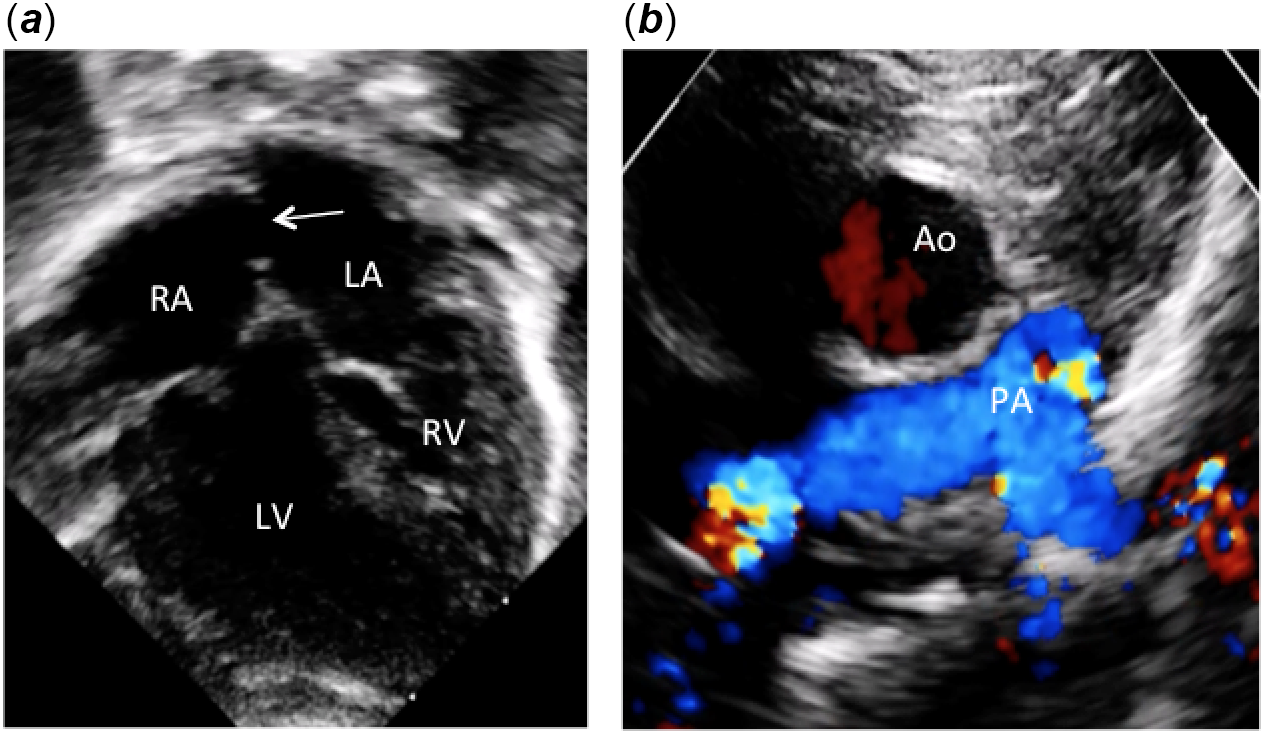

A full-term female neonate with a prenatal diagnosis of “ventricular inversion” was admitted, at birth, to the neonatal ICU with profound cyanosis. Two-dimensional colour Doppler echocardiography showed levocardia, situs solitus of the atria, and discordant atrioventricular connections with l-loop of the ventricle (Fig 1a and c). The ventriculoarterial connections were concordant with the aorta arising anteriorly and right-sided from the right-sided morphologically left ventricle (Figs 1b, 2a and b). The pulmonary artery arose posteriorly and left-sided from the left-sided morphologically right ventricle (Fig 2a). The two great arteries are parallel to each other without spiralisation (Fig 2b). There was a small interatrial communication that required a Rashkind procedure at 3 days of age. The ventricular septum was intact (Figs 1a and 2a). The diagnosis of anatomically corrected malposition of the great arteries [S,L,D] was done, and the patient underwent a successful Mustard operation at 5 months of age. No extracardiac anomalies were detected clinically and by cerebral and abdominal ultrasound examinations.

Figure 1. Apical and parasternal two-dimensional echocardiographic pictures. (a) Apical four-chamber view showing atrioventricular discordance with l-ventricular loop. Note the inverted atrioventricular valve offsetting and the large atrial septal communication (arrow) after Rashkind procedure. (b) Parasternal short axis view showing the aorta located anteriorly and to the right of the pulmonary artery. Ao: aorta; PA: pulmonary artery; LV: left ventricle; RV: right ventricle; RA: right atrium; LA: left atrium.